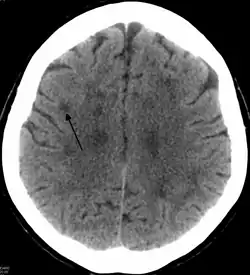

Leukoencephalopathy

Leukoencephalopathy (leukodystrophy-like diseases) is a term that describes all of the brain white matter diseases, whether their molecular cause is known or unknown.[1] It can refer specifically to any of these diseases: